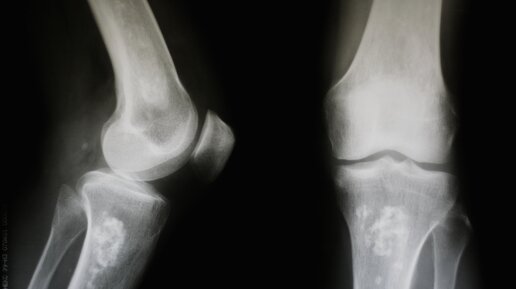

Ситуация, когда болят колени после бега, не понаслышке знакома не только профессиональным бегунам, но и многим далеким от спорта людям. Причины таких болей могут быть весьма разнообразны: от реакции на слишком большую нагрузку до травм или различных заболеваний. Боли в коленях классифицируют по характеру, интенсивности, взаимосвязи с определенным типом движения или нагрузкой, времени проявления и локализации. В некоторых случаях подробное описание того, когда, где и как именно болят колени после бега, может подсказать врачу диагноз...

Почему болят колени после бега: причины и что делать